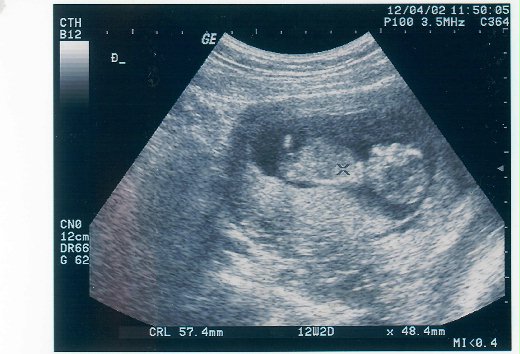

純摯童真彷彿昨日 (生命的兩極圖像,既悲且欣的人生 Part 2) 陳雪麗/華梵大學師資培育中心副教授兼主任 上圖:母親抱我,我週歲。我抱次女瓜瓜,她三個月大。 中圖:我為觀音寶貝設計的祝福卡與瓜瓜出生的紅腳印 下圖:次女超音波照片(懷孕三個多月),調皮仰臥,跟媽媽打招呼! 在部落格登了「生命的兩極圖像,既悲且欣的人生」乙文懷念母親,感嘆生命的兩極圖像:生與死,悲與欣,是人生無可迴避逃離的情景與心情。 貼了姐姐的超音波照片,妹妹一直嚷嚷:「怎麼沒有我?怎麼沒有我?」還好,我這個媽媽還算細心,姐妹倆 (生肖分屬龍馬) 的超音波都留了電腦掃描檔,也妥貼地做了胎毛筆。 祈願一雙寶貝:慈悲如觀音 喜捨龍馬行 為詩預告人世苦空無常: 佛興慈悲為說法 無念無輟海潮音 真觀世事本虛無 鏡花水月轉成空 父母無法一世陪伴,只能寄予祝福與叮嚀: 來日人生有惑,請向觀世音菩薩尋解!